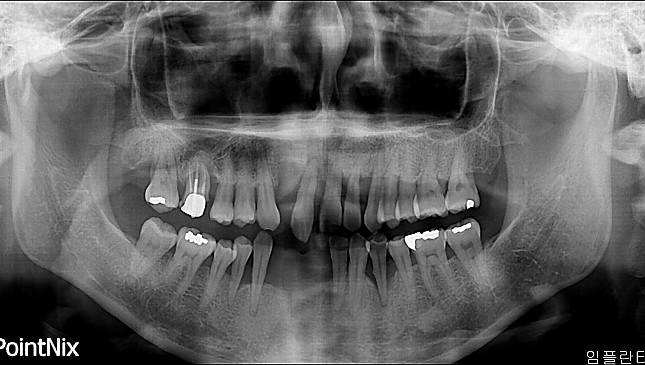

치아살리기 치료 전후 사진

잇몸재생교정 치료 전후사진

잇몸 전체가 무너져 동시다발적으로 죽어가던 치아들을 한꺼번에 살려 냅니다.